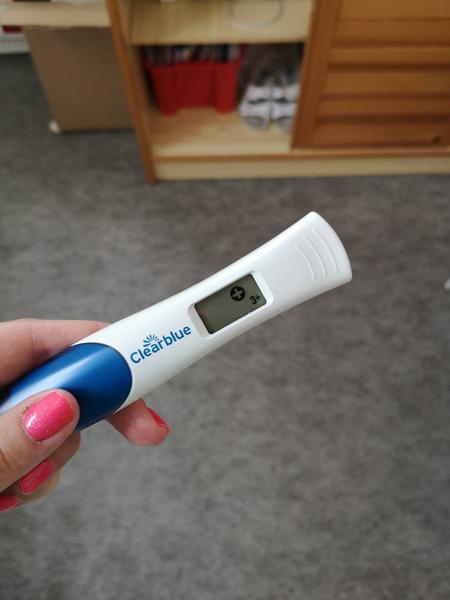

Tak jsem si vcera delala ten digital, a pry jsem tehu, udajne 2-3tyden, pecka, mame hroznou radost, snad ne predcasnou. Doufam ze se vyklindim protoze se porad neceho obavam 😂 meli jste tomi nekdo take tak?jo a stale mi boli jakoby vajecniky, je to normalni? Diky pa

@baruskawh delala jsem si ten digi, ten vysel pozitivne, tak ve stredu jdu k doktoru tak snad tam bude broucek 😇